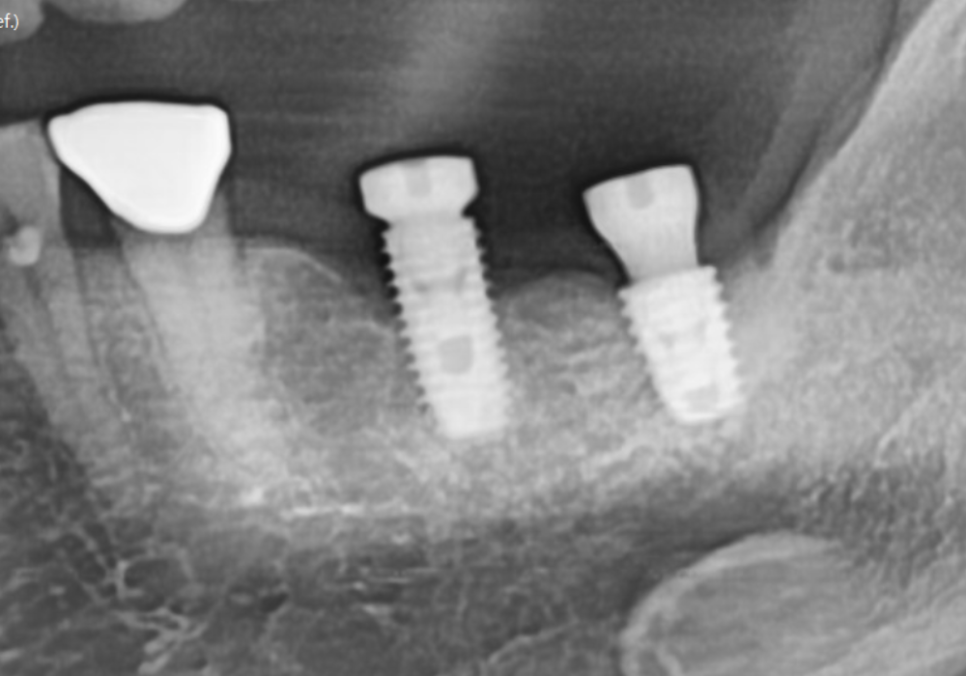

241021

먼저 염증이 심해 제 기능을 잃은

#37 임플란트는 제거하고 재식립하기로 했습니다.

다행히 앞쪽 임플란트 (#36)는

뼈가 많이 녹지 않아 살려서 쓸 수 있겠네요.

#37 부위는 이미 주위염으로 인해

잇몸뼈가 많이 낮아진 상태였기 때문에,

새 임플란트가 단단하게 고정될 수 있도록

꼼꼼한 뼈이식과 함께 재식립 수술을 진행했습니다.